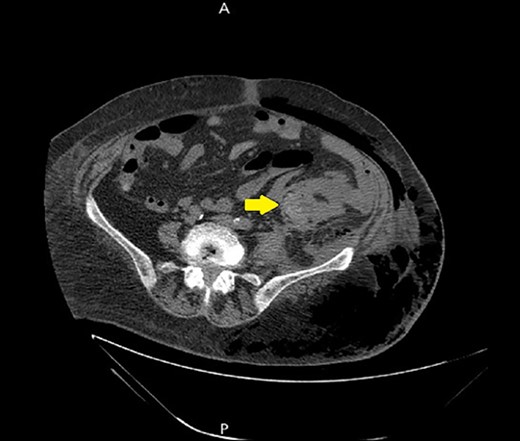

Ultrasound showed extensive subcutaneous soft tissue edema with hyperechoic areas seen in the proximal anterolateral part of the thigh. The initial diagnosis of the condition was a left iliopsoas abscess. Due to the severity of the patient’s symptoms, a non-contrast abdomen and pelvis computerized tomography (CT) scan was done (Fig. 3), which showed a large amount of subcutaneous emphysema within the left flank soft tissues that wrapped anteriorly along the left lower lateral abdominal wall with a small tract of air extending from the left retroperitoneum posterior to the left kidney and extending along the left iliopsoas muscle inferiorly. A skin defect with the underlying abscess collection and air–fluid level was noted (Fig. 4). Another CT scan section saw a soft tissue mass lesion at the distal descending colon (Fig. 5). The abscess drainage was done under CT guidance.

A non-contrast abdomen and pelvis CT scan, which shows a soft tissue mass lesion at the distal descending colon.